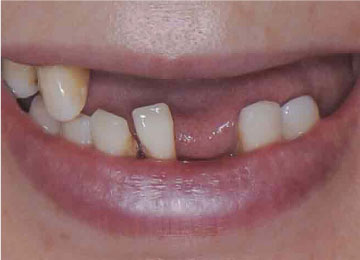

Имплантация зубов: фото "До" и "После"

Фото ДО

Фото ПОСЛЕ

Наведите для просмотра

All-on-4